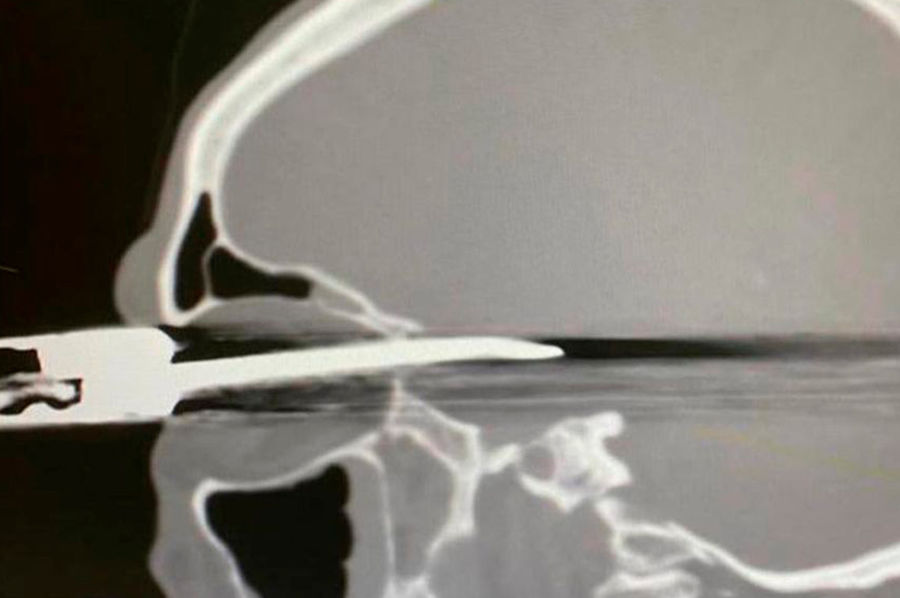

В Кабардино-Балкарии врачи спасли мужчину с ножом в глазу

Врачи Республиканской клинической больницы (РКБ) в Нальчике спасли пациента с проникающим ранением глазницы и черепа, сообщается в Instagram больницы.

После обследования был поставлен диагноз — «проникающее ножевое ранение правой орбиты, полости черепа субарахноидально-паренхиматозное кровоизлияние в правой лобно-височной области с прорывом крови в желудочковую систему. Перелом задней стенки правой орбиты со смещением фрагментов. Инородное тело правой орбиты, полости черепа».

Сначала врачи извлекли нож и обработали рану, затем произвели дренирование раны желудочковой системы головного мозга, то есть удалили жидкое содержимое.

В операции участвовали нейрохирурги, офтальмологи, анестезиологи. Состояние пациента стабильное.